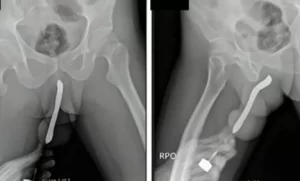

Um homem precisou de atendimento médico de emergência nos Estados Unidos após um episódio inusitado que gerou complicações de saúde. Ele foi levado às pressas para o hospital depois que uma cenoura de aproximadamente 20 centímetros ficou presa em sua cavidade retal, exigindo intervenção médica especializada para a remoção do objeto.

O caso chamou a atenção da equipe de emergência, que prontamente avaliou a situação e realizou o procedimento necessário para garantir a segurança do paciente. No entanto, ao ser questionado pelos médicos sobre como o objeto foi parar ali, o homem não conseguiu fornecer uma explicação clara.

Casos como esse não são isolados e frequentemente exigem atendimento especializado para evitar complicações, como perfurações ou infecções. Profissionais da saúde alertam que, em situações semelhantes, a busca por ajuda médica imediata é essencial para evitar riscos graves à saúde.